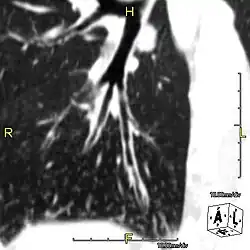

- Bronquiectasias.

O defeito na estrutura do cílio ocasiona seus batimentos incoordenados e inefetivos, alterando a remoção de secreção de muco e das partículas inaladas, culminando em rinites, sinusites, otites, bronquites e pneumonias. Todos estes são quadros recorrentes e persistentes. Entretanto, a bronquiectasia é a complicação pulmonar predominante.